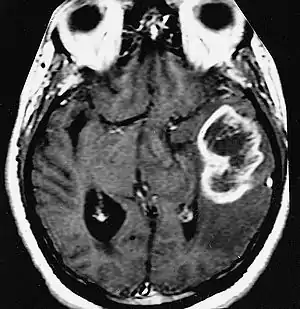

| MRI showing a ring-enhancing lesion in the brain of a patient with glioblastoma multiforme | |

A ring-enhancing lesion is an abnormal radiologic sign on MRI or CT scans obtained using radiocontrast. On the image, there is an area of decreased density (see radiodensity) surrounded by a bright rim from concentration of the enhancing contrast dye. This enhancement may represent breakdown of the blood-brain barrier and the development of an inflammatory capsule. This can be a finding in numerous disease states. In the brain, it can occur with an early brain abscess as well as in Nocardia infections associated with lung cavitary lesions. In patients with HIV, the major differential is between CNS lymphoma and CNS toxoplasmosis, with CT imaging being the appropriate next step to differentiate between the two conditions.[1]